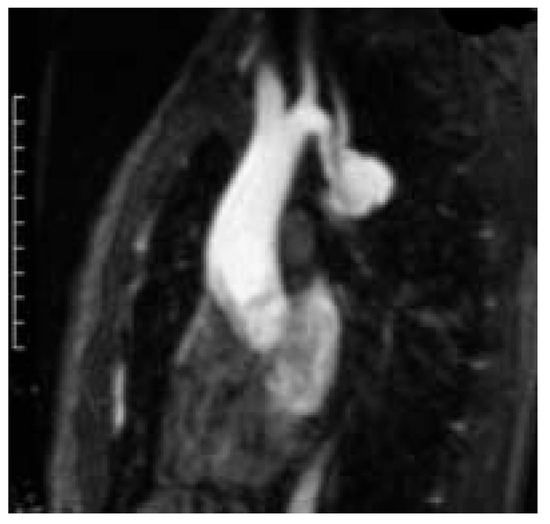

The young patient with coarctation recovered extremely well without any cardiac, neurologic or bleeding complication and was discharged after one week of hospitalisation. At 6 months follow-up she did well and had a normal blood pressure (systolic pressure 110) both at rest and at exercise under a mild dosage of beta-blocker. Postoperative magnetic resonance imaging demonstrated a patent aortic bypass and the complete exclusion of the pseudoaneurysm (Figure 7).

Figure 7. Postoperative MR-angiography shows the patent ascending-to-descending aortic bypass, an ascending aorta-to-left carotid bypass and the transposition of the left subclavian artery to the left carotid artery.